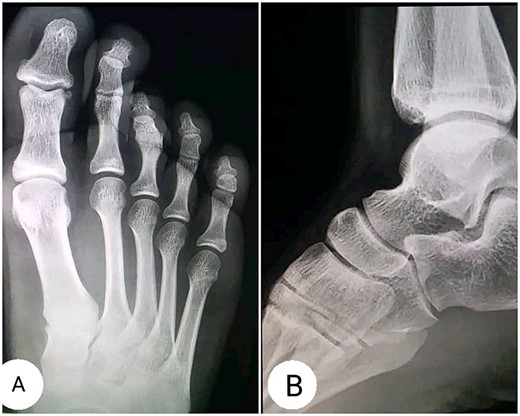

The clinical examination revealed flexion contracture of the third digit of the right foot with dislocation of the proximal interphalangeal (PIP) joint, limited passive and active extension of the second and fourth digits and the presence of little thickness in the skin over the dorsal aspect of the first metatarsophalangeal joint of the foot (Fig. 1). By palpation, there is a non-tender pseudotumor within the plantar aspect of the right foot, without any scare over it (Fig. 2). The X-ray radiographs show inferior dislocation of the PIP joint of the third digit, without any signs of bone lesions or previous fracture (Fig. 3). Ultrasound echomyography shows a significant and heterogeneous increase in the size of the Flexor Digitorum Brevis muscle of the foot. Magnetic resonance imaging (MRI) before gadolinium injuction (Fig. 4) and after gadolinium injuction (Fig. 5) shows a heterogeneous hyperenhancement with irregular margins within the Flexor Digitorum Brevis muscle.

X-Ray radiographs showing (A) inferior dislocation of the PIP joint of the third digit; (B) Lateral radiograph showing no abnormalities.